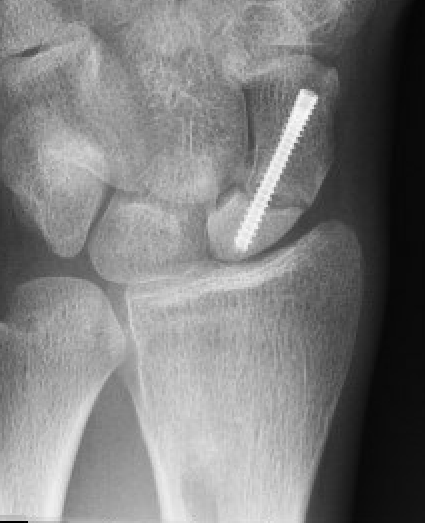

Xray

Increased sclerosis proximal pole consistent with AVN

Increased sclerosis proximal pole post surgery